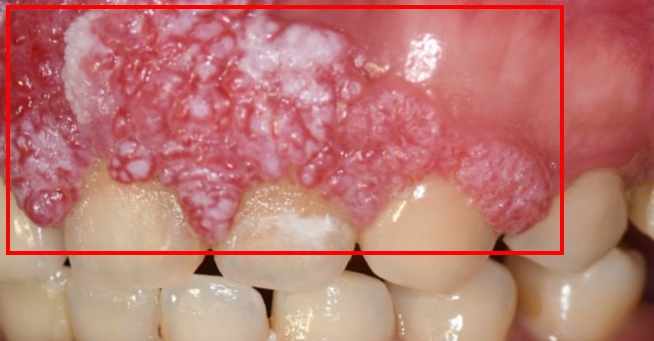

40歲的許小姐於2024年前往中山醫學大學附設醫院(以下簡稱中山附醫)口腔顎面外科就醫,確診為上顎牙齦癌,須切除大範圍上顎骨,不僅影響外觀,口內鄰近腫瘤的10顆牙齒亦需一併拔除。醫療團隊於術前運用電腦數位模擬技術,精準規劃腫瘤切除範圍、術後牙齒重建位置,並模擬將植體植入顴骨,以彌補上顎骨缺損。

邱昱瑋主治醫師也提醒,即使不抽菸、不喝酒、不嚼檳榔,仍有罹患口腔癌的可能。若民眾發現口腔內出現長期不癒的潰瘍、腫塊或不明原因疼痛,應及早就醫檢查,把握黃金治療時機。